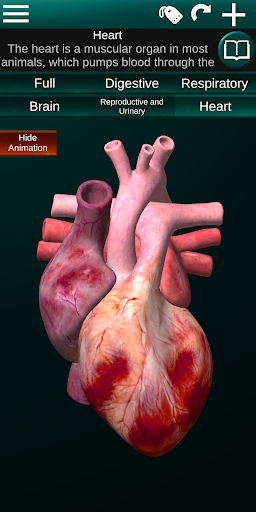

Показує 3D анатомічну модель основні органи людського тіла та опис кожного з них.

* Серце, що включає передсердя, шлуночки, аорту і одушевлення цього органу.